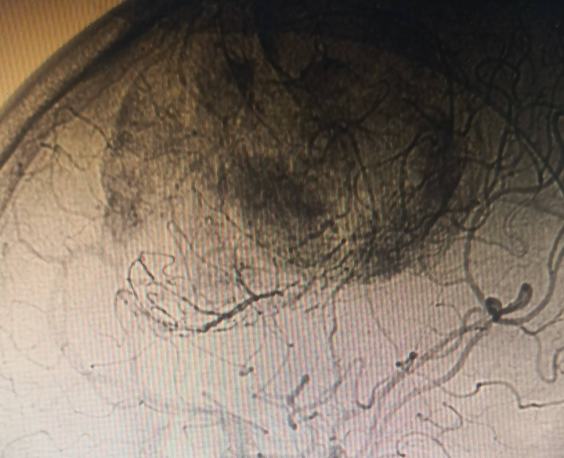

患者系中年女性,因出现偏侧肢体活动不灵和头痛症状,经检查发现颅内大脑镰旁长有一直径7cm的巨大肿瘤。肿瘤位于大脑的运动功能区,血供丰富,这一区域的手术风险极大。在决定手术治疗之前,神经外科医生与患者家属进行了充分的沟通,详细解释了手术的必要性、可能的风险和并发症,包括出血、感染、血管和神经损伤以及脑功能障碍等。家属在充分了解情况后,同意进行手术。面对这一复杂病例,我院迅速组织了由神经外科、麻醉科、心内科、输血科等多个科室的专家团队进行会诊,共同制定了先介入栓塞,再手术切除的治疗方案。

神经外科血管介入组曲友直副教授、崔刚副教授和高攀主治医师对肿瘤进行了瘤栓塞治疗,有效减少了肿瘤的血供,为后续的手术切除降低了风险。栓塞治疗后,神经外科王睿智副主任、高李贵副教授和董全主治医师在麻醉科、心内科、输血科等科室的全力配合下,凭借精湛的医术和丰富的临床经验,成功为患者切除了病变。手术过程中,麻醉科吕建瑞主任团队全程监控患者的生命体征,确保麻醉安全;心内科团队随时准备应对可能出现的心脏问题;输血科团队则确保充足的血液供应,以备不时之需。多学科的通力合作,为手术的成功提供了坚实的保障。